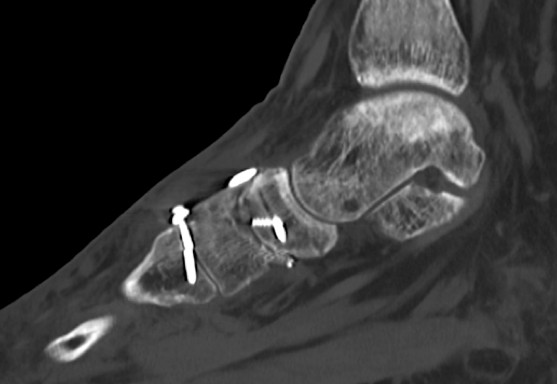

Im CT vom September 2017 ergab sich noch kein Durchbau der Arthrodesen, aber ein Bruch der das TMT 2 überbrückenden Schraube.

6.- 09/2017 Schraubenbruch